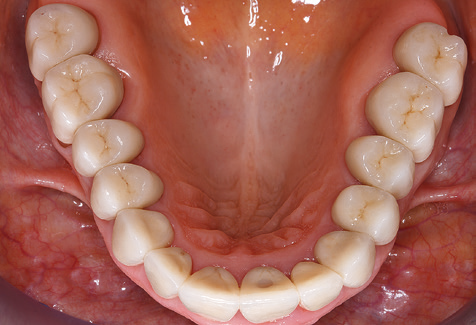

Für den klinischen Langzeiterfolg des parodontal kompromittierten Patienten ist die standardisierte und regelmäßige risikoadaptierte Betreuung im Rahmen der UPT der zentrale Baustein des Behandlungserfolgs. Dies gilt in besonderer Weise für Patienten, die nach erfolgreich abgeschlossener parodontaler Sanierung mit Implantaten versorgt wurden (Abb. 11a und b).

Vor Beginn der prothetischen Versorgung ist es ratsam, den Patienten über die im Rahmen der UPT erforderlichen zeitlichen und finanziellen Aufwendungen (zwei bis viermalige UPT pro Jahr, lebenslang) zu informieren. Dies trägt wesentlich dazu bei, die Compliance des Patienten zu sichern. Darüber hinaus ist die Praxis bei der Bereitstellung der räumlichen und personellen Ressourcen für die Betreuung der parodontal sanierten Patienten gefordert.